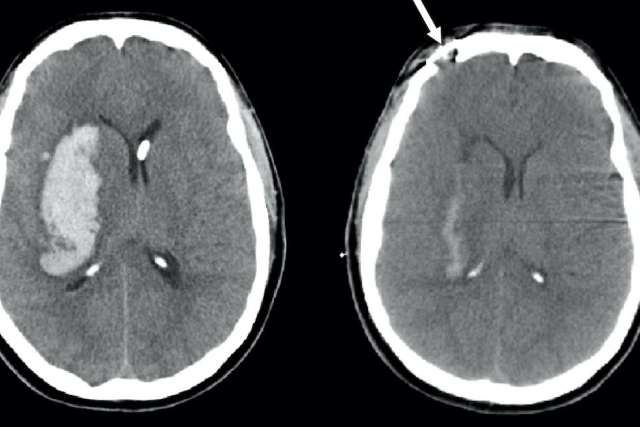

Studies in animals and humans that recorded activity across different brain regions have found that activity patterns change after a stroke, suggesting that the damaged brain can “re-map” functions from one area to another. In the last few years, innovative new tools have enabled researchers to start looking at individual neuron activation in real-time. By using a technique called two-photon fluorescence microscopy that causes neurons to light up when they are activated, researchers can observe which neurons in the animal brain are called upon during certain activities and determine if neurons that survived a stroke can assume the function of those that were lost.

“We thought, now that we have this tool where we can record the activity of neurons in the brain, we could directly test this question,” says Dr. Zeiger. By learning the functions of individual neurons, then causing a targeted stroke, the researchers could use the new technique to observe how the neighboring neurons responded.

Mice gather information about their environment primarily through their whiskers, and each whisker transmits sensory signals to a specific group of neurons. By destroying the neurons coded to a specific whisker, the researchers could look at whether neurons for a different whisker took over for their lost neighbors.

That’s what the re-mapping hypothesis predicts would happen in the brain. “If the hypothesis were true, we would see cells that survived the stroke start to respond to that whisker that had the stroke,” Dr. Zeiger says. “What we found was that that didn’t happen.”

“That was pretty strong evidence against this remapping hypothesis,” Dr. Zeiger says. “It did not seem like there was bulk recruitment to take over the function which had been lost to stroke.”